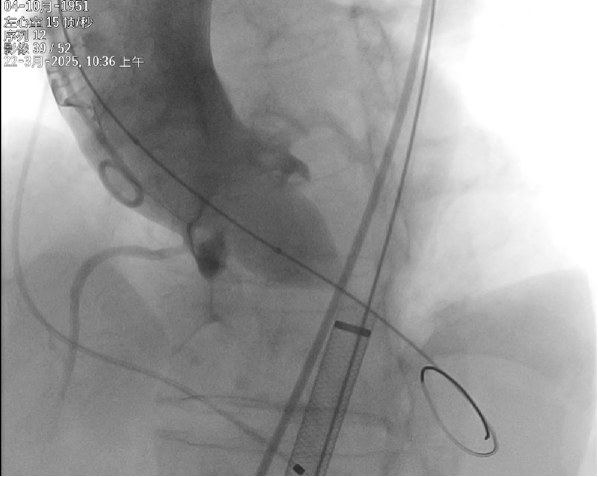

Magpie22球囊预扩

输送系统根部定位